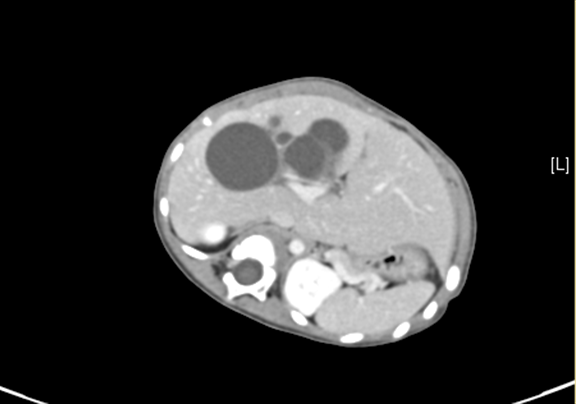

术前CT检查:

动脉期

上腹部增强CT:符合胆总管囊肿。

将0.625mm双源薄层CT资料的静脉期和动脉期Dicom格式文件导入海信CAS系统。

通过调节窗宽窗位调整CT序号,对肝实质,胆囊,胆总管,下腔静脉,肝动脉、门静脉及肝静脉等进行三维重建;系统自动计算肝脏体积。